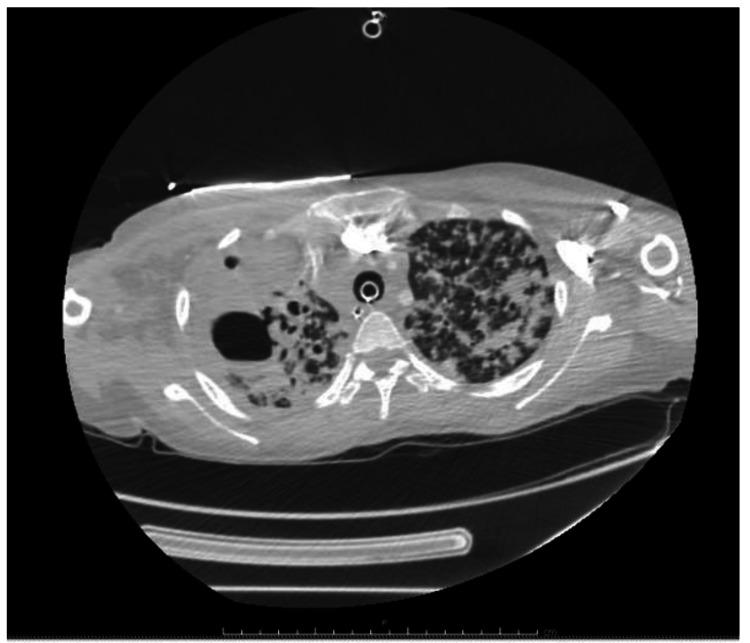

Tuberculosis (TB) disease affects a large population worldwide but is often missed. Early diagnosis can be challenging at times due to failure to include TB in the differential diagnoses. Tuberculosis is a treatable disease but it can lead to undesirable consequences if left untreated. Here we report a case of a young Guatemalan woman presented with respiratory failure and extensive lung opacification on imaging who went into cardiac arrest. Post resuscitation, workup was significant for (TB) on sputum smear. Despite appropriate treatment, she expired. The aim of this paper is to summarize TB complications that directly contribute to mortality as many clinicians do not consider TB as an immediate cause of death.

结核病在全球影响着大量人口,但常常被漏诊。由于在鉴别诊断中未将结核病纳入考虑,早期诊断有时具有挑战性。结核病是一种可治疗的疾病,但如果不治疗,可能会导致不良后果。在此,我们报告一例年轻的危地马拉女性病例,该患者出现呼吸衰竭,影像学检查显示肺部广泛浑浊,随后发生心脏骤停。复苏后,痰涂片检查发现(结核病)呈阳性。尽管进行了适当治疗,她仍不幸去世。本文的目的是总结直接导致死亡的结核病并发症,因为许多临床医生并不认为结核病是直接死因。